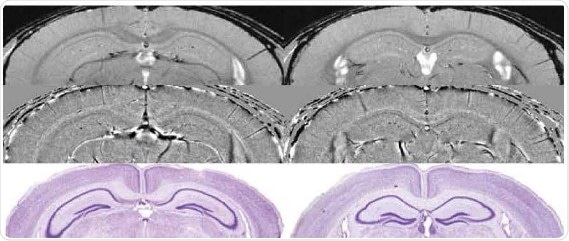

ln vivo mouse brain with 19.5 µm resolution at 15.2 Tesla

Comparison of micro-structures in the mouse brain measured at 15.2 T by using high resolution SWI with histological Nissle staining (below}. Image Credit: Bruker BioSpin Group